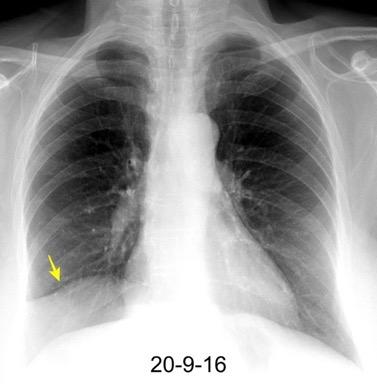

Parálisis frénica transitoria tras cirugía de válvula aórtica

Parálisis frénica transitoria post cirugía cardiaca (10%).

Puede acompañarse de atelectasia del LII.

Benjamin JJ et al. . Left lower lobe atelectasis and consolidation following cardiac surgery: the effect of topical cooling on the phrenic nerve. Radiology 1982